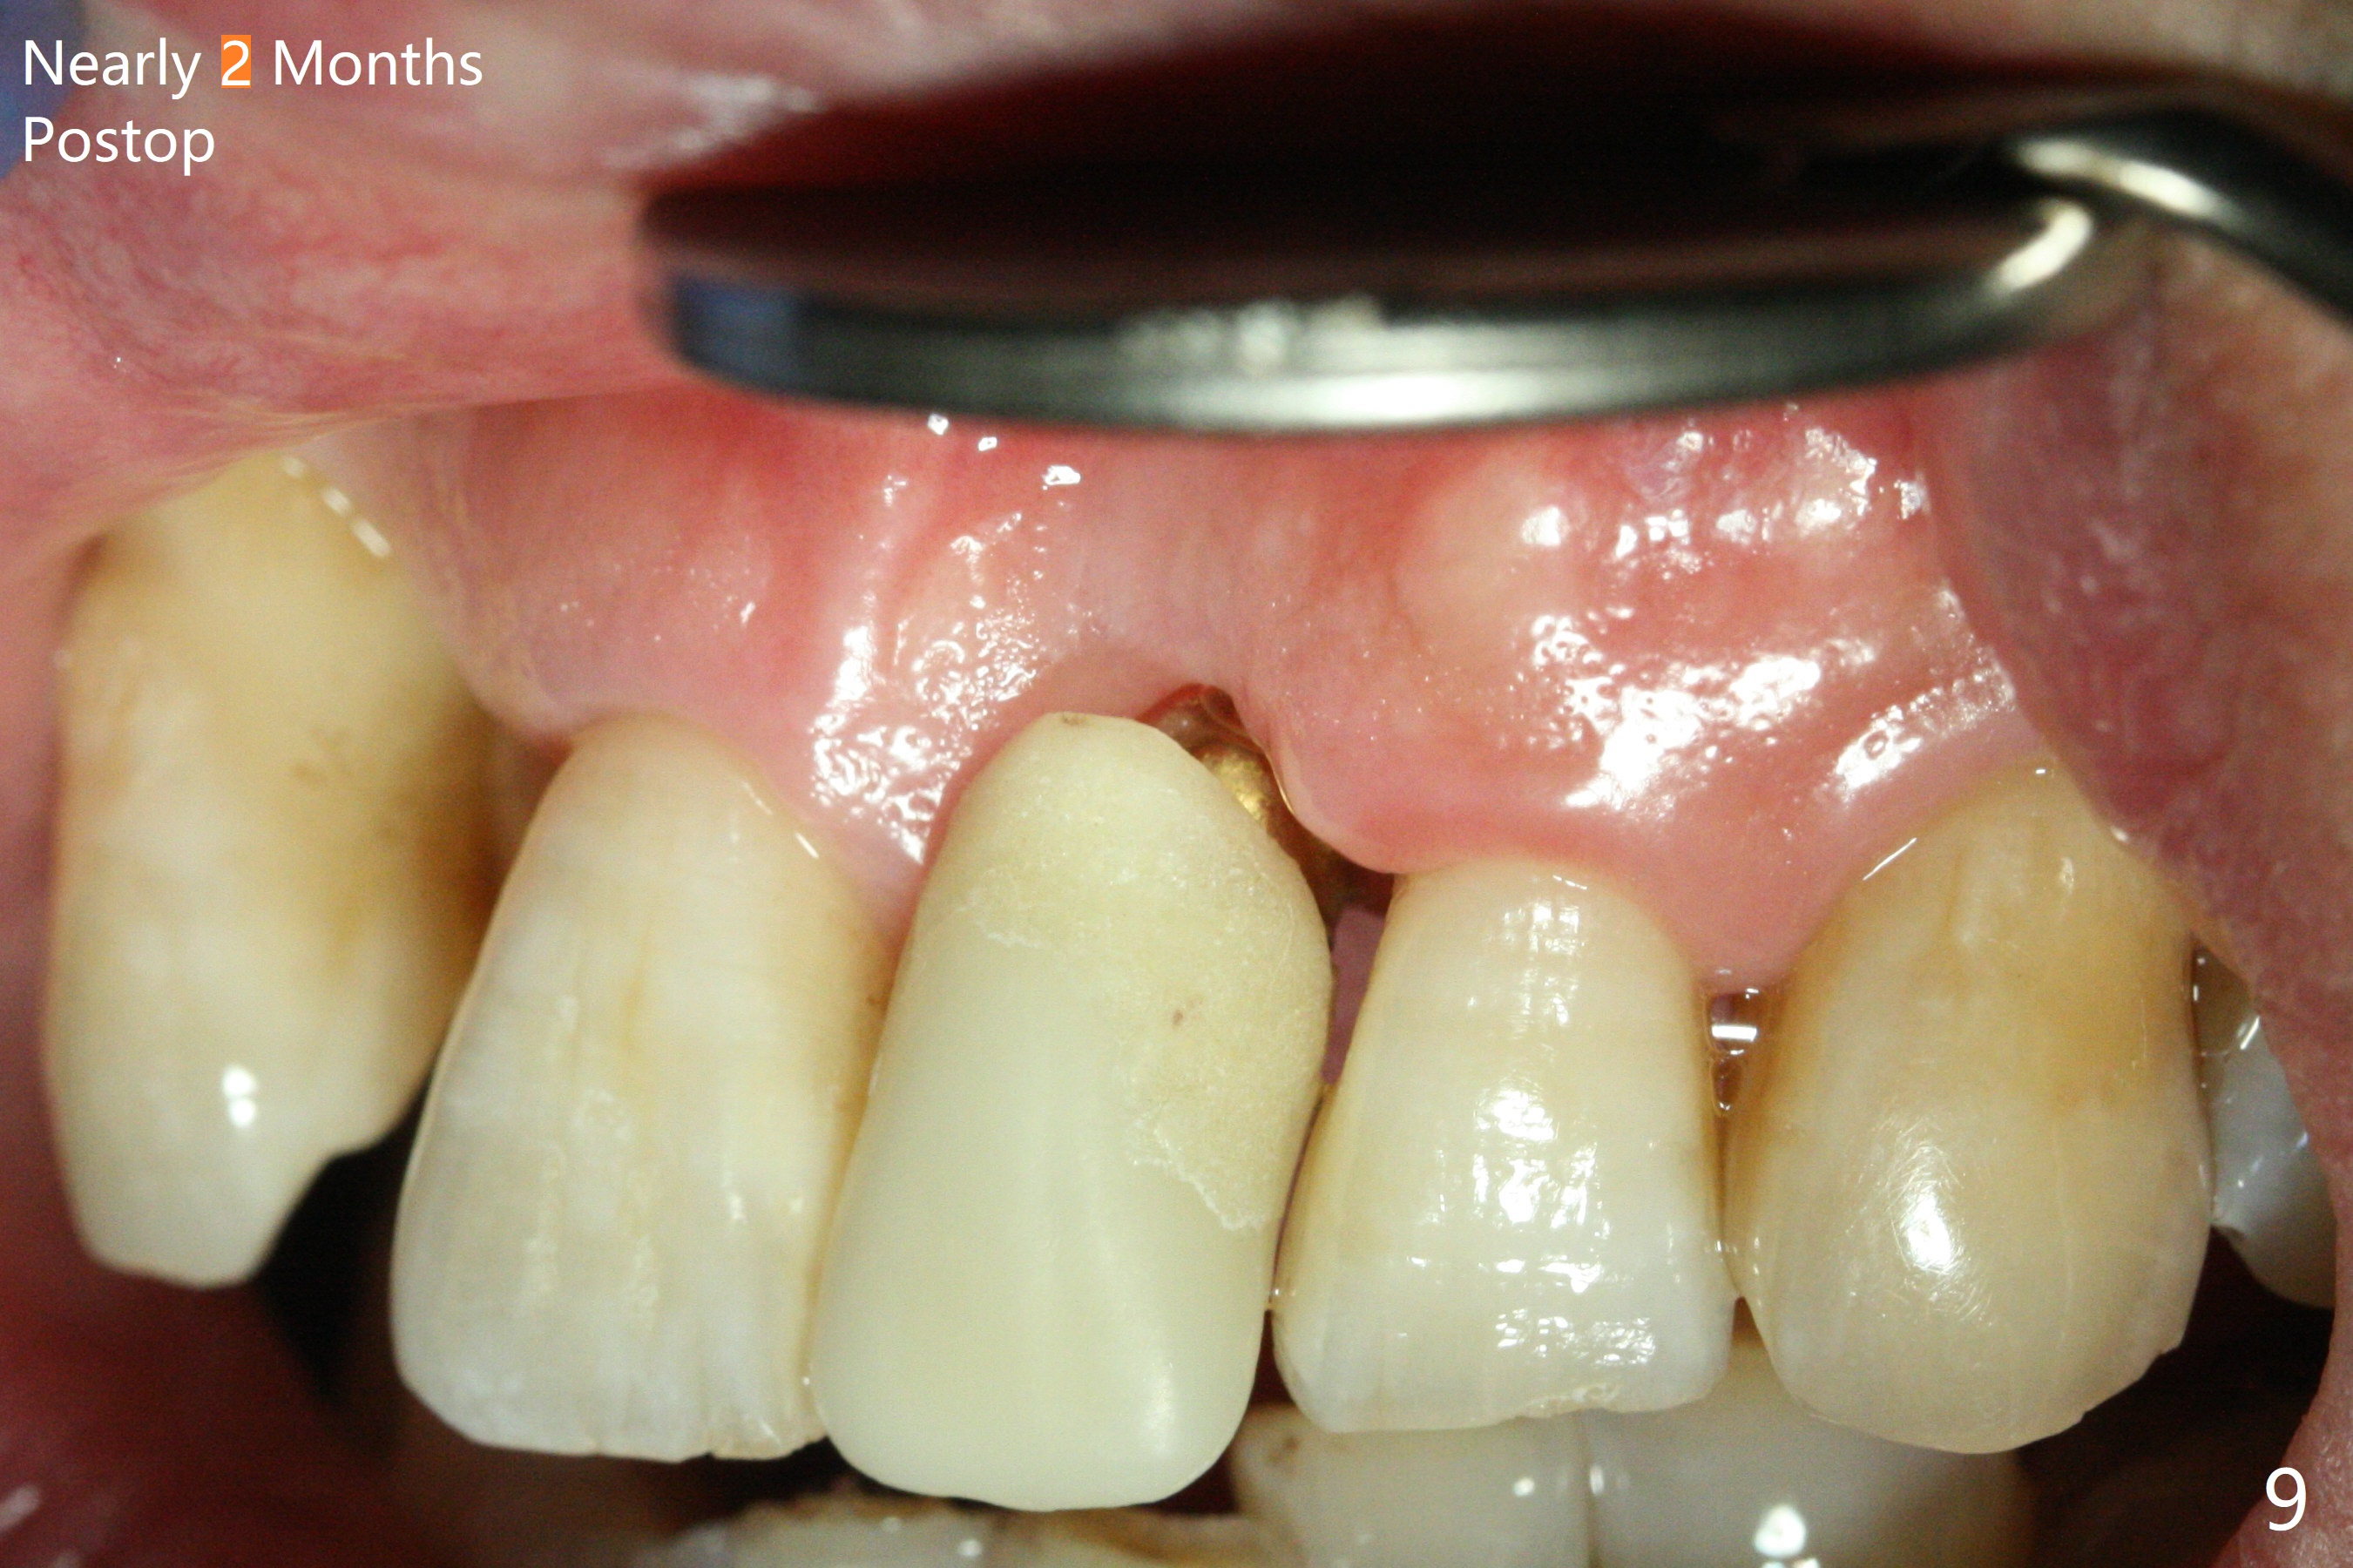

Immediately preop PA confirms loss of the buccal plate at #9 (Fig.1 *). In contrast the palatal crest is ~ 4 mm subgingival (WNL) after extraction. When initial osteotomy reaches 18 mm, there is moderate hemorrhage, probably due to close to the nasal floor (Fig.2 red dashed line). Following sequential osteotomy, a 3.8x15 mm dummy implant is placed partially (Fig.3 (pink: apical osteotomy)). After placement of an implant with the same dimension as the dummy's (Fig.4), PRF is laid against the inner surface of the buccal defect and allograft (Fig.5 *) is packed mainly in the buccal gap before and after insertion of a 4.5x5(4) mm abutment. The patient is satisfied with the immediate provisional (Fig.6: 1 week postop). The buccal margin of the provisional is shortened with exposure of bone graft to facilitate gingival downgrowth (Fig.6: 1 month postop). The buccal plate seems to collapse nearly 2 months postop (Fig.8 *), probably due to loss of the bone graft. The abutment is exposed buccally (Fig.9). The margin of the abutment is reprep and the provisional is relined so that the margin of the provisional is palatal to the buccal gingival margin. In 2-3 weeks, a temporary abutment will be used to bulk the buccal gingiva. The gingiva seems to have downgrown; the buccal plate collapse appears normal nearly 3 months postop (Fig.10). The patient is more concerned about cross bite at #7. A temporary abutment is not used. The bone graft remains in place 3.5 and 4.5 months postop (Fig.11,12 *). Between 3 and 4 months postop, the mesial surface of the abutment has been trimmed (Fig.12 >). Since the mesial surface of the tooth #10 will be reduced (white curved line) to correct the upper dental midline, an angled abutment (red line) seems to be necessary to shift the provisional distal.